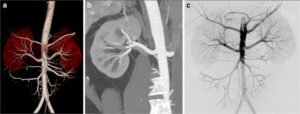

CT renal angiography is a specialized imaging procedure that uses computed tomography (CT) technology to visualize the blood vessels in and around the kidneys. It

CT peripheral angiography is a diagnostic imaging procedure that uses computed tomography (CT) technology to visualize the blood vessels in the peripheral (outer) parts of